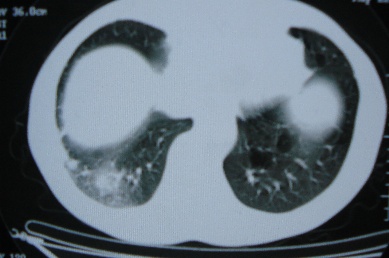

ct10716,男,59岁。发热咳嗽一天,咯血一次入院。

病灶中心有低密度,气体,病灶周围炎性浸润可能为肺脓肿,量体温、查个痰就是了,但肺脓肿一般都多少会有点兄水的。左肺下局部密度减低,小叶中心肺气肿。

病灶边缘较模糊,中心见低密度影及少量气影,宽基与胸膜相连,周围见炎性浸润,考虑右下肺脓肿。

病灶边缘较模糊,中心见低密度影及少量气影,宽基与胸膜相连,周围见炎性浸润,考虑右下肺脓肿。建议治疗后复查。

右下肺病灶,边缘模糊,中心见低密度坏死区及气体影,结合病史较短,以发热为主,考虑右下肺脓肿,建议抗炎治疗后复查。